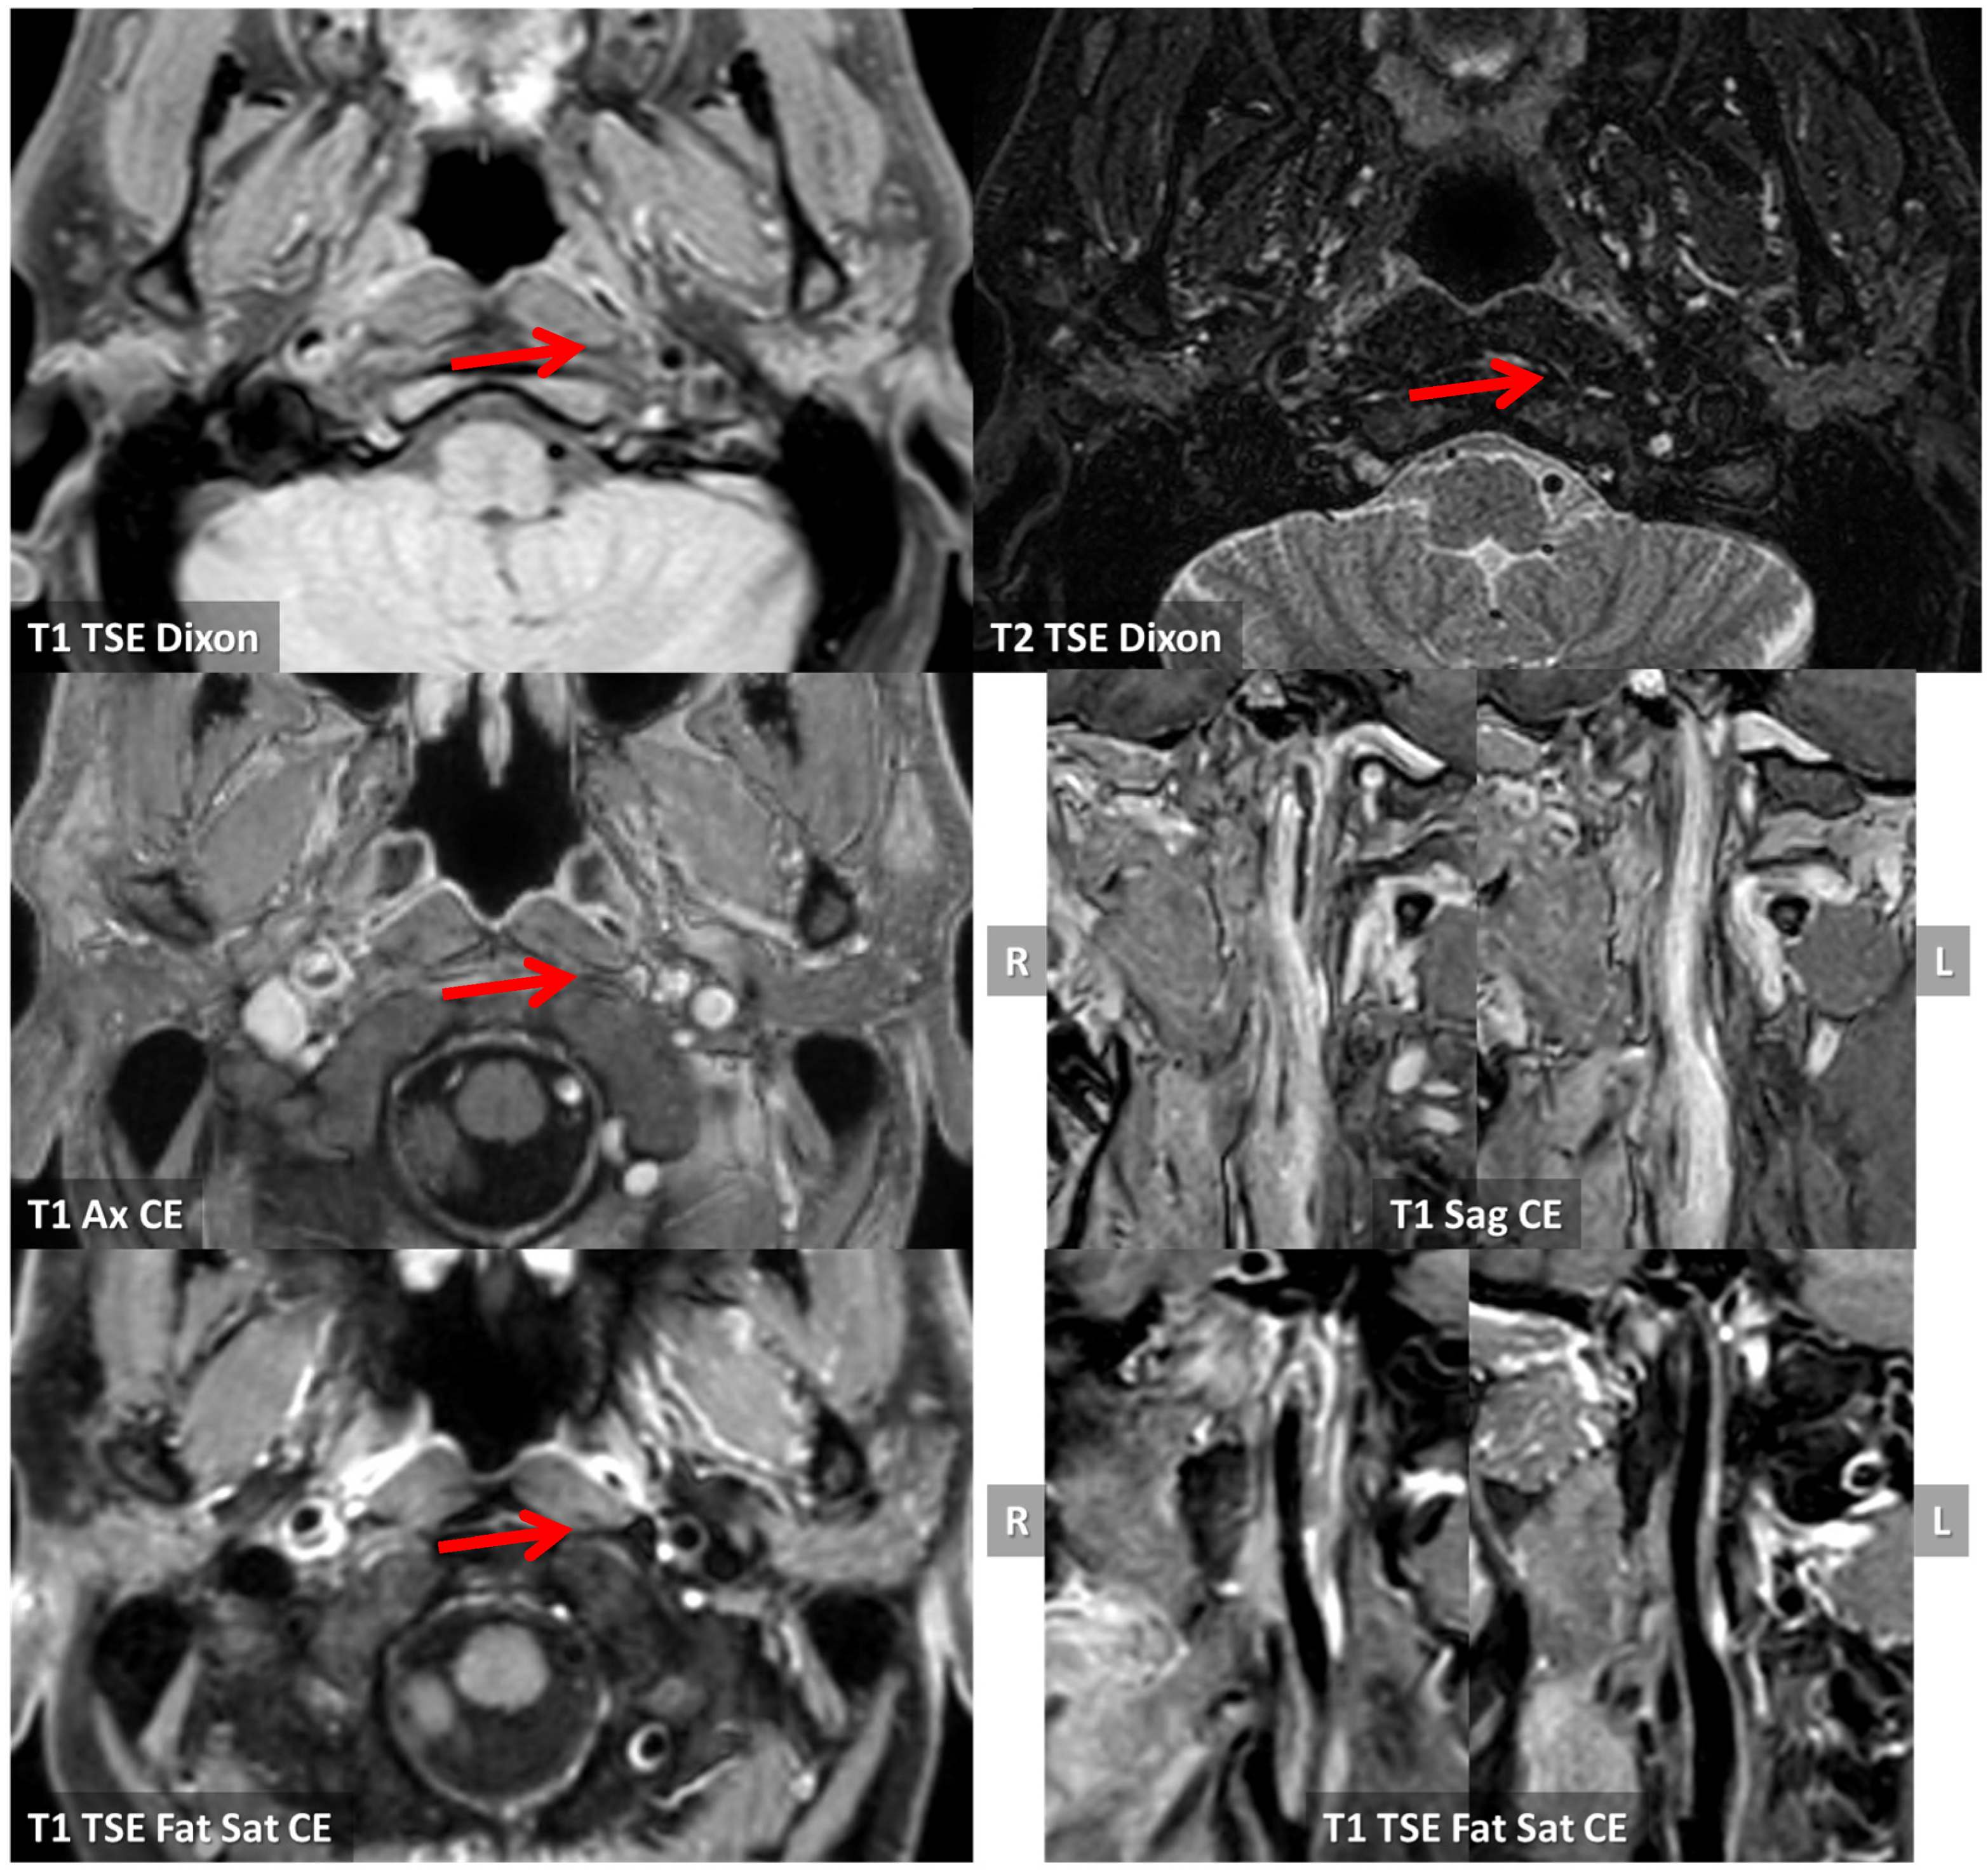

3.1. Case 1

3.2. Case 2